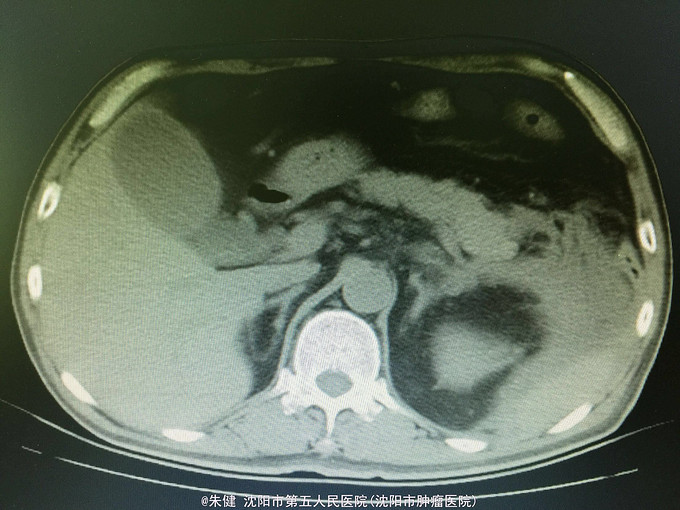

男,52岁 主诉:上腹部胀痛30小时, 现病史:30小时前饮酒后引起上腹部胀痛,持续性,逐渐加重,累及腰背部,恶心,呕吐数次胃内食物,无发热,未治疗,因不见好转来诊;病来无心悸、气短,排气、排便可,排尿正常。

一般状态可,腹部平坦,未见肠形及蠕动波,剑突下及左侧上腹部压痛,轻度肌紧张,未及包块,无移动性浊音,肠音正常,肾区无扣痛。 辅助检查:血常规:白细胞13.6*10^9/L,中性83.3/L;尿淀粉酶:214U/L,上腹部CT:左侧胸腔积液,左肺下叶可见斑片及索条状影;胆囊增大,胆道内未及结石影;胰腺形态及密度正常,胰腺尾部周围可见索条状影及积液影。

诊断:急性胰腺炎 处理:给予禁食、补液、抗炎及抑肽酶治疗,病情逐渐好转,一周后出院。